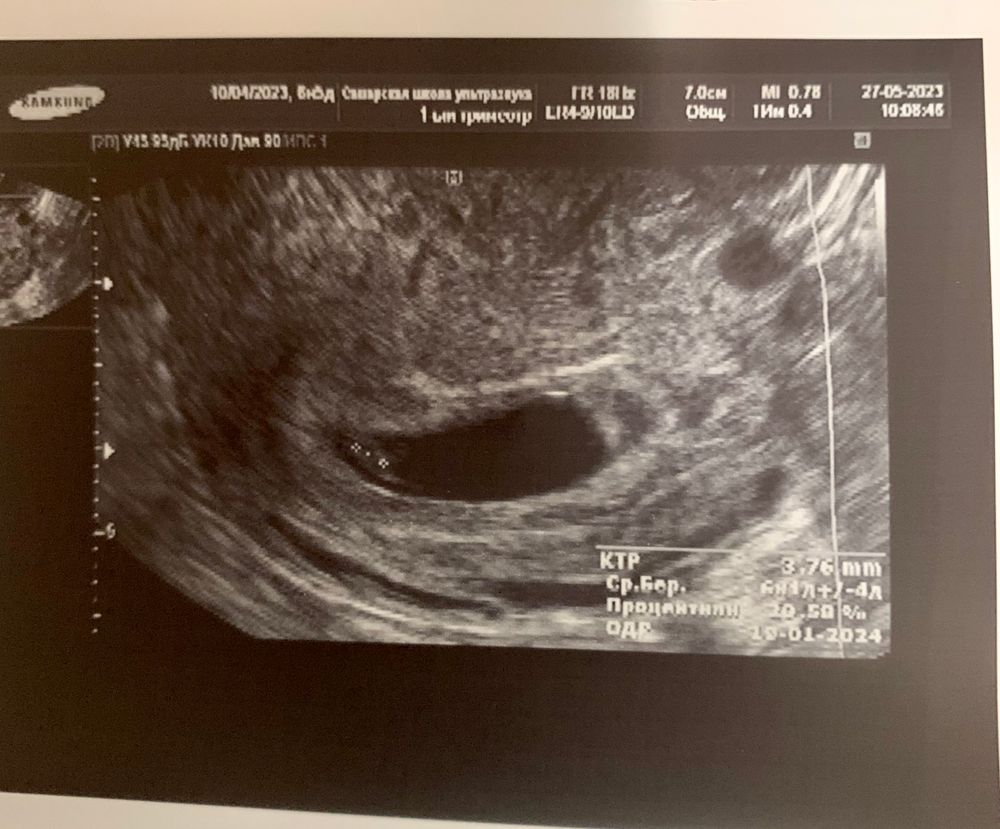

Анна, первый день последних месячных 10.04.23. Но у меня 10 мая хгч был уже 1705 Изображение

elena, на первом узи 1 пя 2,5 мм. Узист произнес конечно фразу : тааак, а где второе… Через 2 недели увидели тоже 1 эмбрион и то, еле еле «дотянулись». Он так расположился, в самом дне матки. В общем, вроде 1 у нас))) на скрининге уже точно будет видно. Да и такое явление, как исчезающий близнец никто не отменял. Но никто 100% мне не говорил что было 2😂 Изображение

Отслойка хориона 7нед Сходила на узи ))